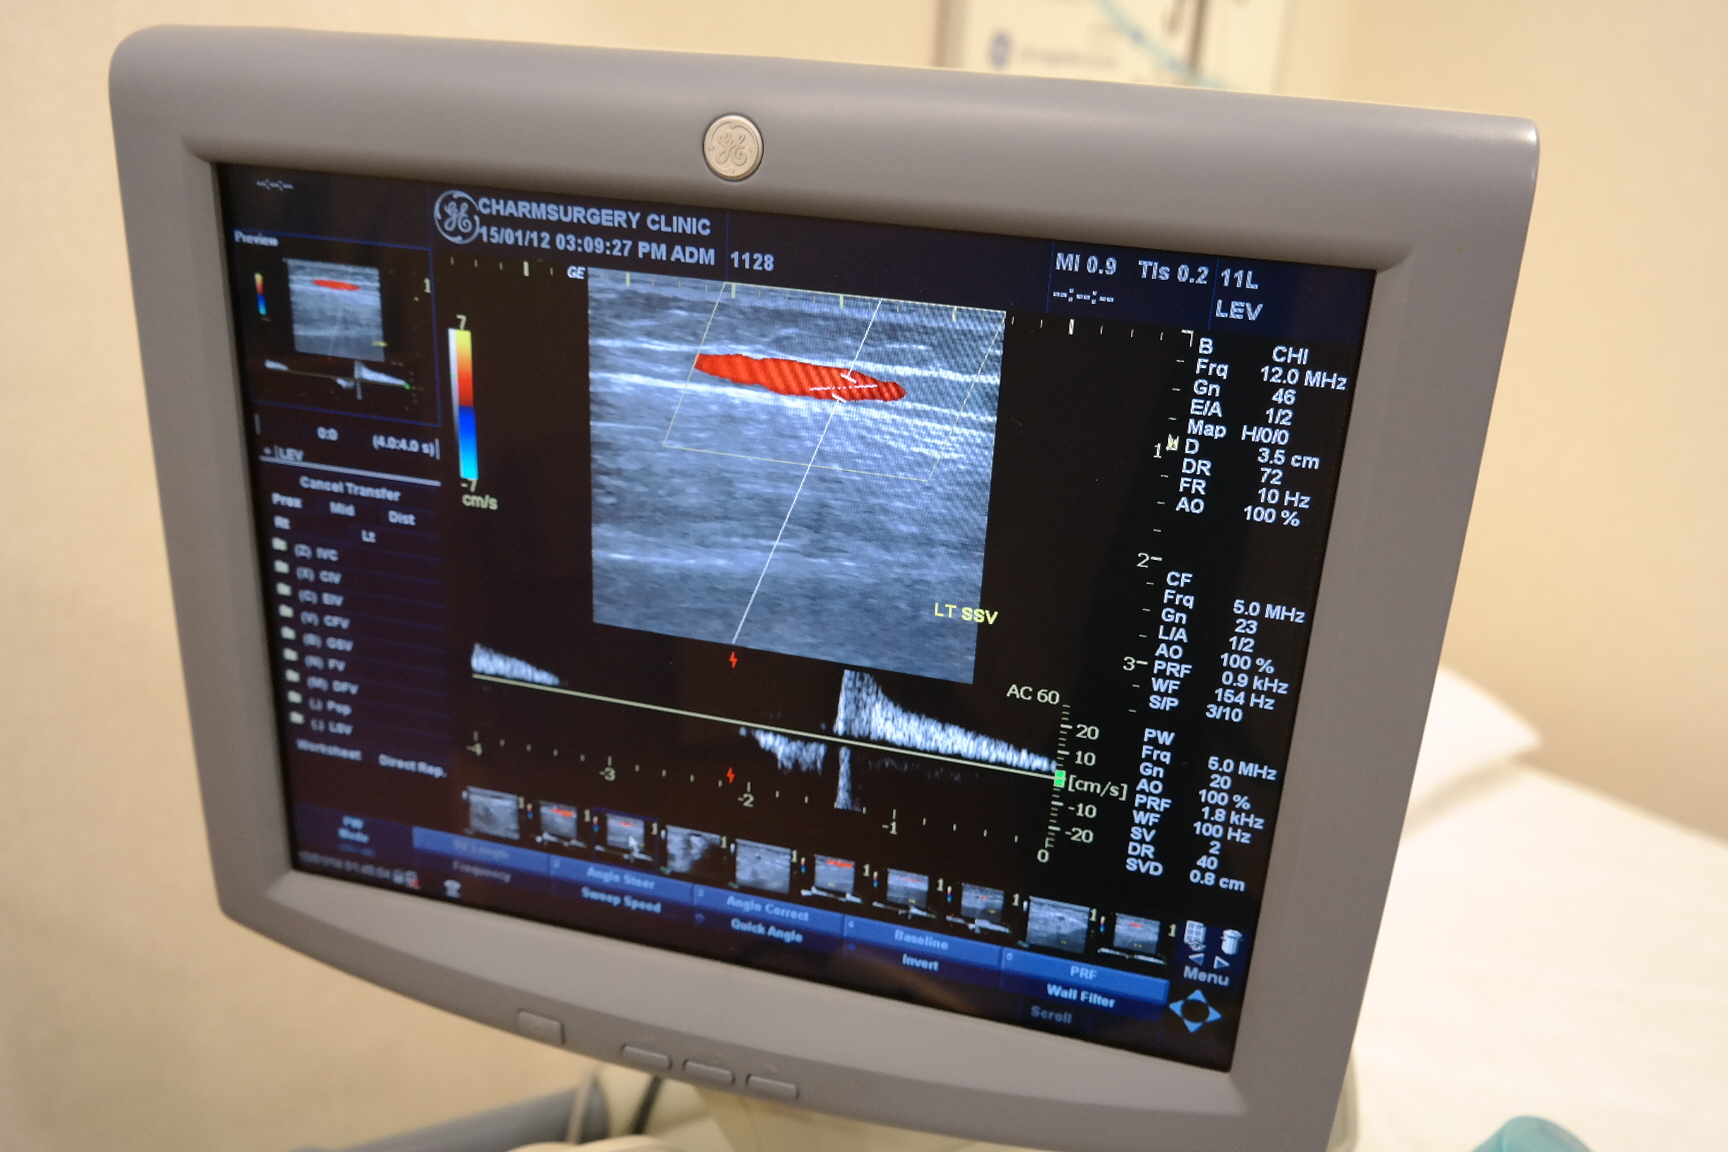

역류가 나타나는 사진입니다.

사진과 같이 역류되는 뿌리 혈관이 밑에 숨에 있다면

주사요법만으로 치료해서는 안되며

반드시 뿌리 혈관을 잡아주는 수술적 치료를

동반해야 재발을 막을 수 있습니다.